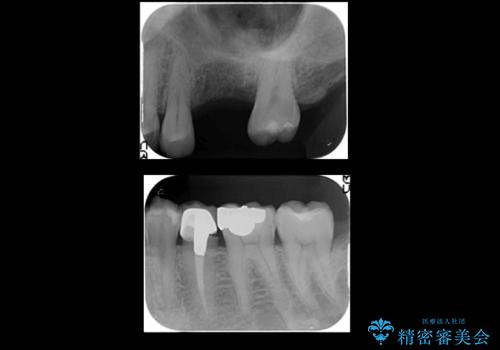

上の奥歯のインプラント、全体的な虫歯治療

- 上の奥歯が無いところにインプラントを希望して来院。

インプラントの向かい合わせの歯や隣の歯の虫歯治療も併せて行なっています。